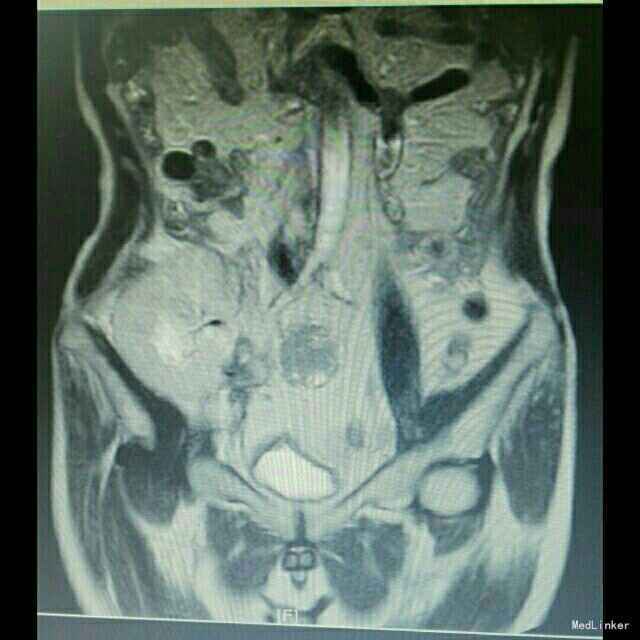

入院后行移植肾区磁共振检查,提示移植肾区多发性淋巴结肿大;彩超提示移植肾下极可见不规则低回声区,凸向体表,位于脂肪层与肌层之间,范围约49*11mm